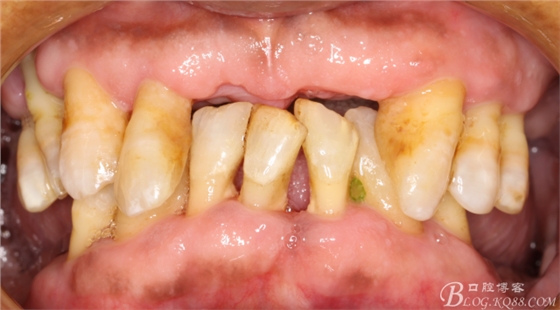

越到后期患者越想保留自己的牙齒,但是有些牙齒是我們無(wú)法保護(hù)的了的,即使是保留了可能對(duì)以后的修復(fù)效果有影響,

患者首先對(duì)我很信任,因?yàn)橛兴畠和扑]過(guò)來(lái),要求最好的修復(fù)效果,能少拔牙就少拔牙,保留一顆是一顆,

對(duì)待這樣的病人 溝通起來(lái)很簡(jiǎn)單,首先本身?xiàng)l件就不好,能達(dá)到怎樣的效果患者都能滿意接受,

于是給患者做以下治療方案:

1:保留

上頜--15、13、23、24、25

下頜--44、43、42、41、32、33、34

并做根管治療,改變冠根比例,觀察恢復(fù)效果

2:對(duì)保留的牙齒徹底的牙周治療,

3:拔除其他松動(dòng)牙